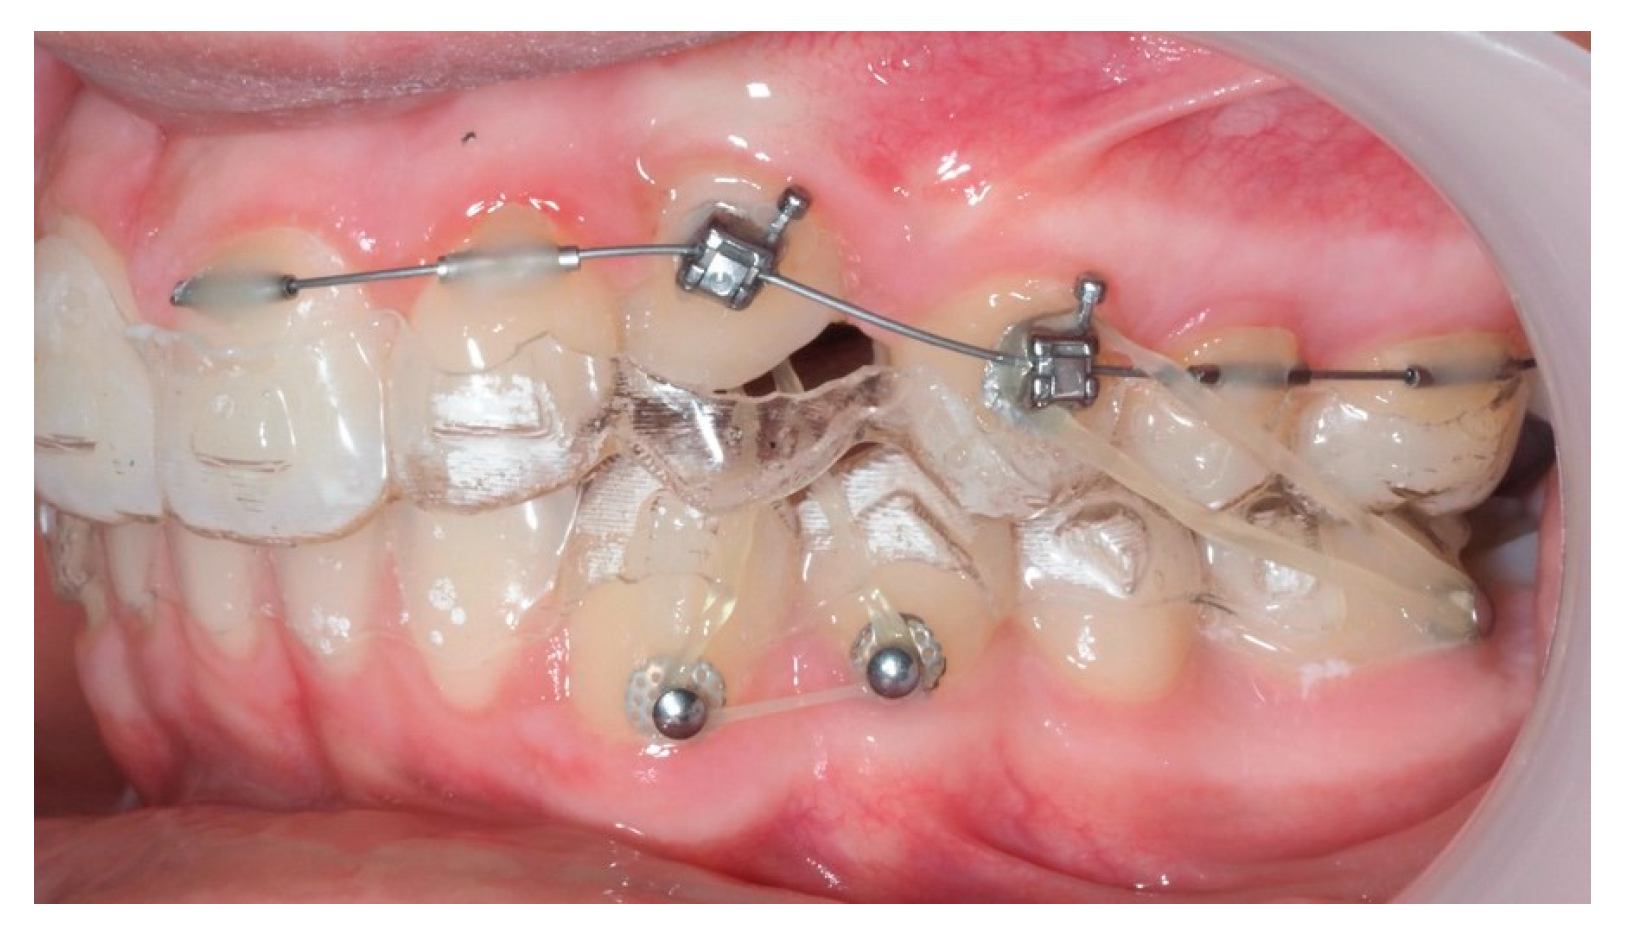

Following initial distalization, a sectional fixed appliance was bonded from tooth 11 to 26. On tooth 24, a bracket with a metallic ligature was used to support Class II elastics. Mini-tubes were bonded on teeth 22, 25, and 26, and the aligners were trimmed accordingly (Figure 16). A ligature wire connected the palatal button on the canine to a 0.014” nitinol archwire (Figure 17).

Figure 16.

Sectional fixed appliance from teeth 11 to 26, with support for Class II elastics to improve sagittal relationship; 14 months after the surgery.

Figure 17.

Ligature wire attached to a 0.014” nitinol archwire on the palatal surface of the canine; 14 months after the surgery.